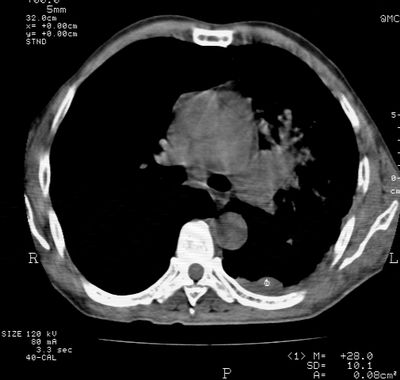

标题: CT24000:M65,胸痛,胸闷月余,既往慢支,肺气肿,肺心病 [打印本页]

标题: CT24000:M65,胸痛,胸闷月余,既往慢支,肺气肿,肺心病

左肺门肿块,相应支气管闭塞,左肺上叶、舌叶大片及散在高密度影,部分呈不张改变,两肺纹粗乱,左侧胸腔积液。考虑左侧中央型肺癌伴阻塞性改变。

左肺门见巨大软组织肿块影,直径约--,境界清,左上肺叶支气管变窄,左上肺舌叶见大片状密实影,余肺纹理增多、紊乱、纤细、部分网格状,两肺透亮度增高,纵隔内见增大多发淋巴结影,心影略左偏,左侧少量胸腔积液。

左侧中央型肺癌伴左上肺舌叶不张、纵隔淋巴结转移,左侧少量胸腔积液。